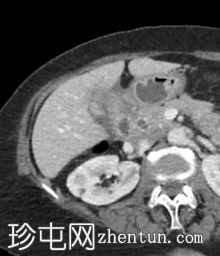

轴位增强扫描(门静脉期)

2.jpg

胆囊缩小,囊壁增厚,提示慢性炎症改变。胆囊(底部)与十二指肠(球部)腔之间可见细小瘘管,胆囊内及肝内、肝外胆管内均可见气体(胆道积气)。

远端空肠内嵌顿一枚较大的胆结石(3.5 cm),近端空肠袢扩张,回肠袢、末端回肠及结肠均塌陷。